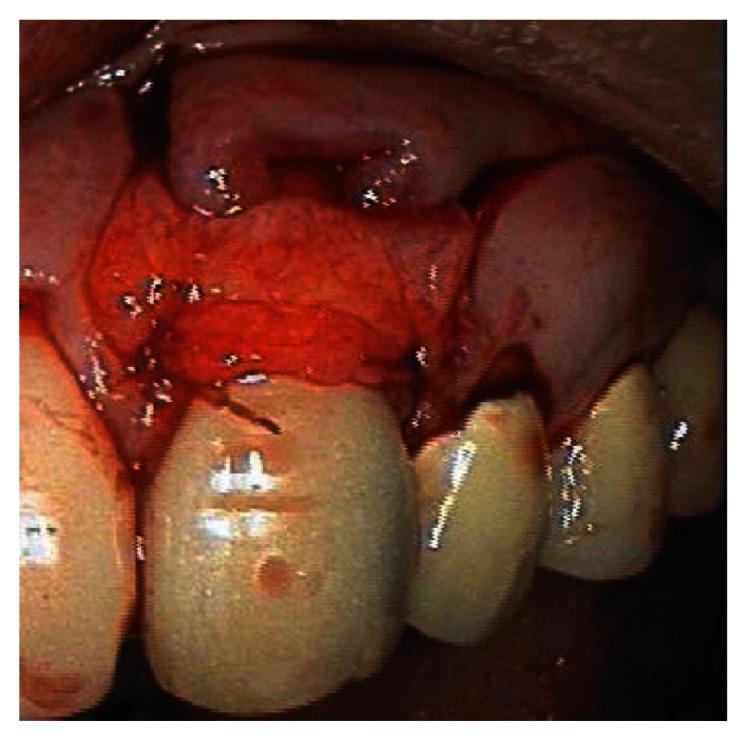

This case report describes the treatment of a maxillary canine that had 4 mm of marginal gingival recession. The exposed root had been previously restored with a composite class 5 restoration. The restoration was removed and the root planed and demineralized. The root was then covered by a subepithelial connective tissue graft harvested from the palate. The flap was coronally positioned to completely cover the graft and exposed root. The healing was photographed post-operatively at one month, six months, and seven years. Root coverage increased to 100% after seven years. The zone of attached gingiva also increased.